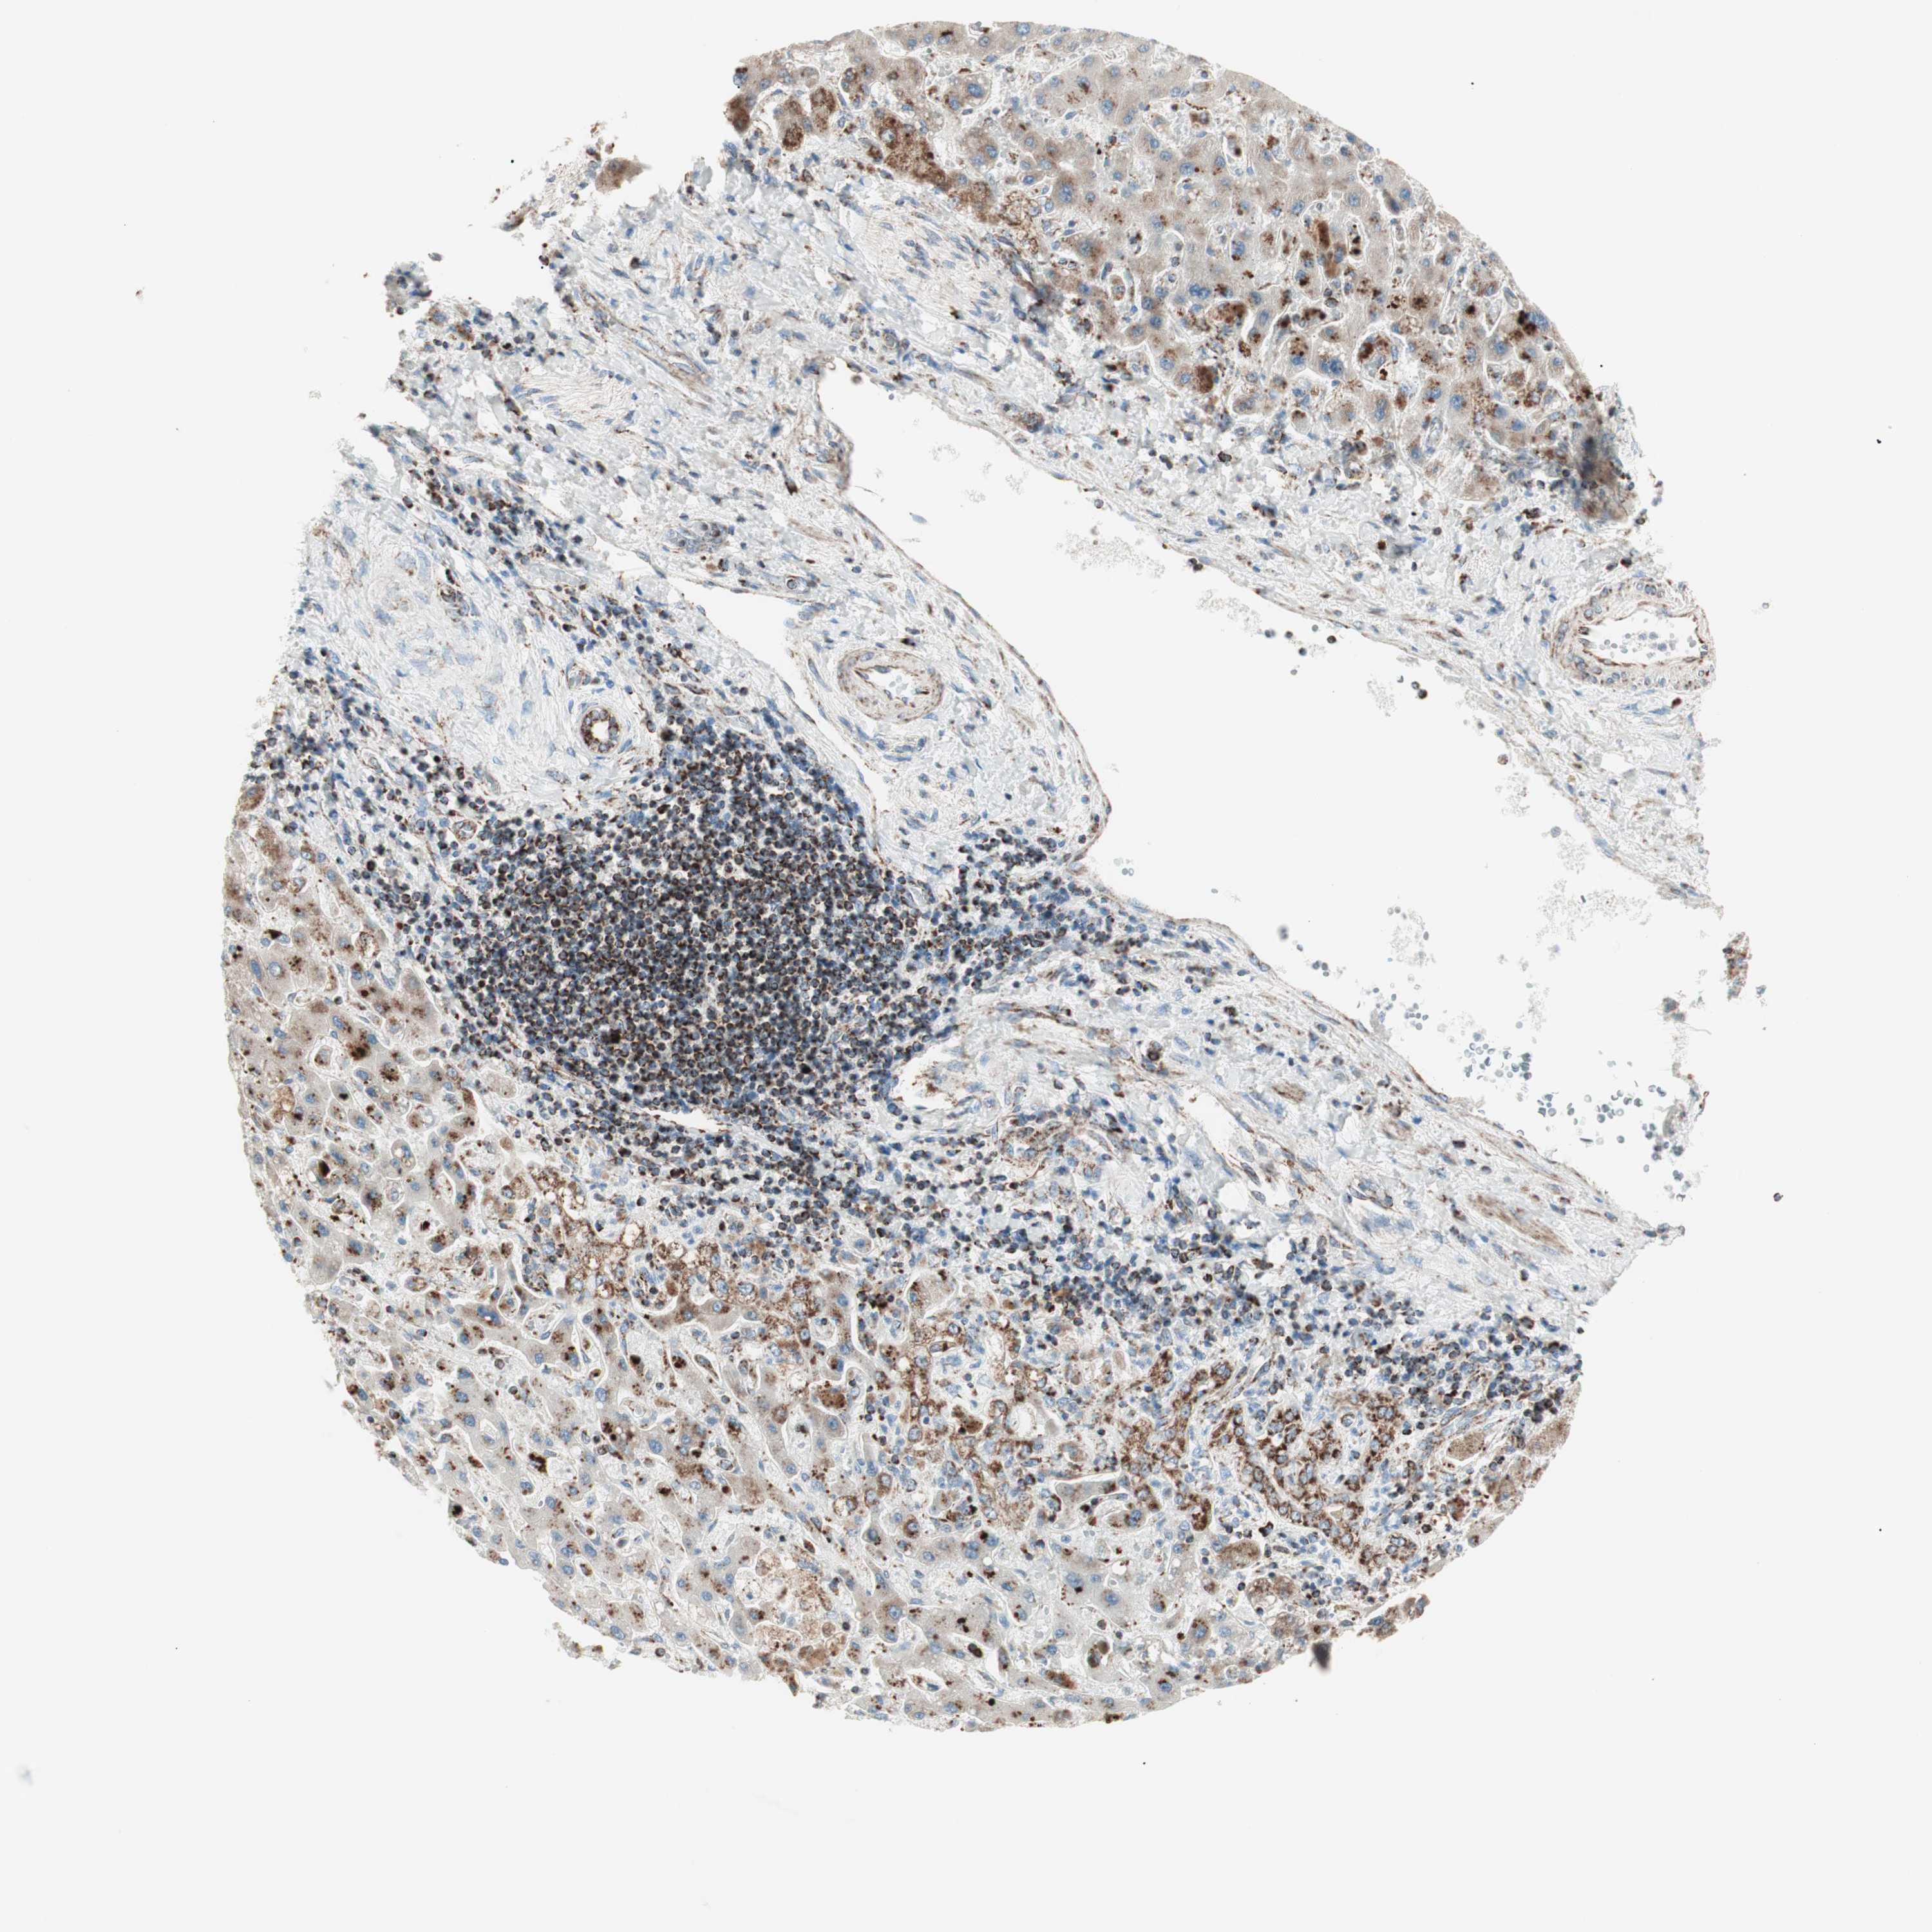

LIVER CANCER - Protein expressioni

A mouse-over function shows sample information and annotation data. Click on an image to view it in a full screen mode. Samples can be filtered based on level of antibody staining by selecting one or several of the following categories: high, medium, low and not detected. The assay and annotation is described here.

Note that samples used for immunohistochemistry by the Human Protein Atlas do not correspond to samples in the TCGA dataset.

Antibody stainingi

Antibody staining in the annotated cell types in the current human tissue is reported as not detected, low, medium, or high, based on conventional immunohistochemistry profiling in selected tissues. This score is based on the combination of the staining intensity and fraction of stained cells.

Each image is clickable and will lead to virtual microscopy that enables deeper exploration of all samples and also displays staining intensity scores, fraction scores and subcellular localization as well as patient and tissue information for each sample.

Antibody HPA011562

Antibody CAB005585

Staining

High

Medium

Low

Not detected

Intensity

Strong

Moderate

Weak

Negative

Quantity

>75%

75%-25%

<25%

None

Location

Nuclear

Cytoplasmic/membranous

Cytoplasmic/membranous,nuclear

Cholangiocarcinoma

Carcinoma, Hepatocellular, NOS